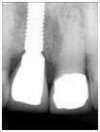

L’extraction de l’incisive et la mise en place de l’implant est faite dans la même séance ainsi que la préparation de la deuxième incisive.

L’empreinte est réalisée et la prothèse sera posée le soir même.